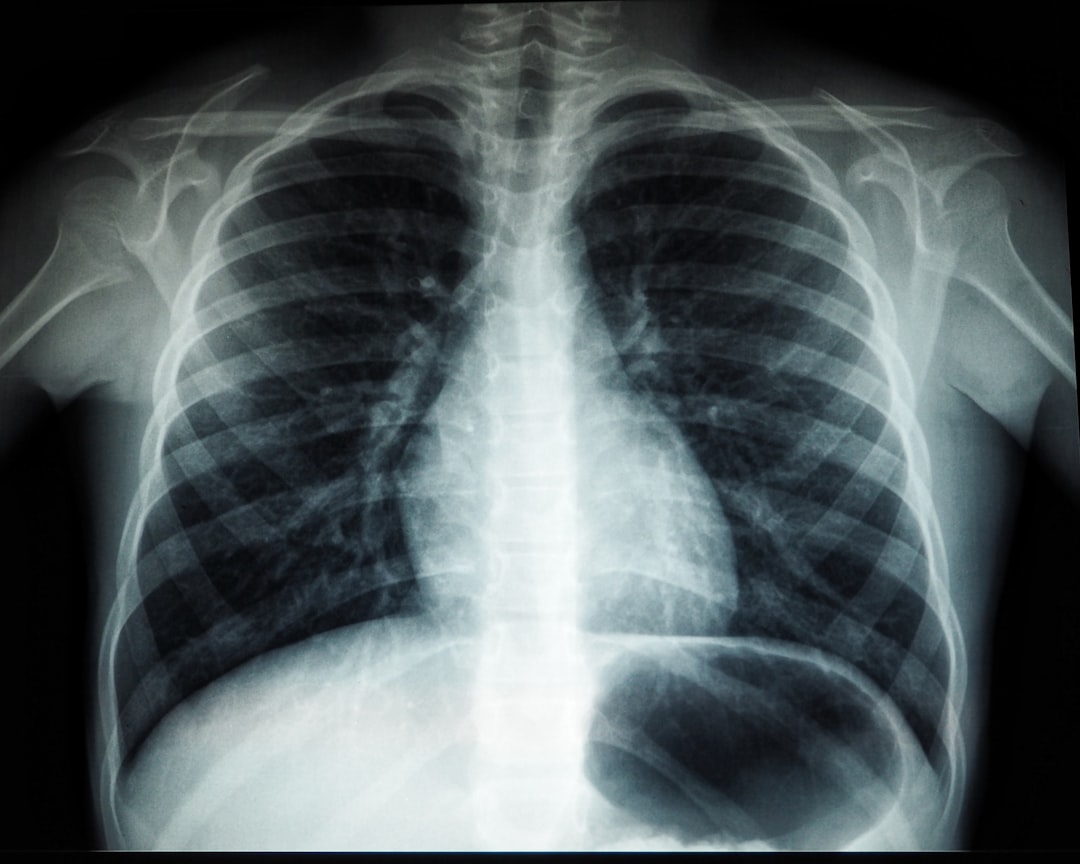

검사 당일, 지정된 보건소에 방문하면 담당자가 결핵 검사를 진행하게 됩니다. 일반적으로는 기숙사 입소용 결핵 검사로 X-ray 촬영 또는 피부 반응 검사를 통해 이루어집니다. 이때 몸 상태에 따라 적절한 검사를 진행하게 되는데, 검사 방법은 상대적으로 간단합니다. 결과는 보통 몇 일 후에 알림을 받을 수 있습니다. 걱정하지 마세요, 모든 과정이 잘 진행된다면 심각한 문제는 발생하지 않으니까요!

A3: 결핵 검사는 주로 X-ray 촬영 또는 피부 반응 검사를 통해 이루어지며, 간단한 과정입니다. 추천하는 보건소에 문의하여 필요한 절차를 확인하세요.